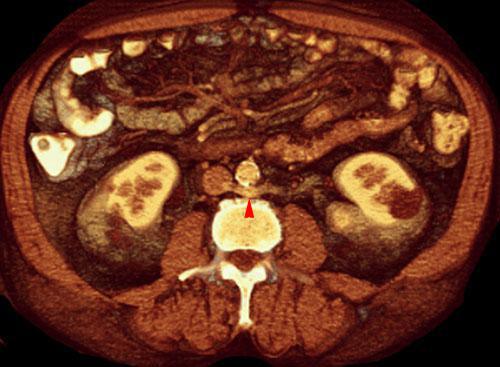

El AngioTC arterial y venoso es la técnica de elección para la demostración de la unidad o multiplicidad, de venas renales deechas y las variantes retroaórtica y circumaórtica de la vena renal izquierda.

Las reconstrucciones volumétricas tridimensionales juegan un papel muy importante en el estudio y comprensión de estas variaciones